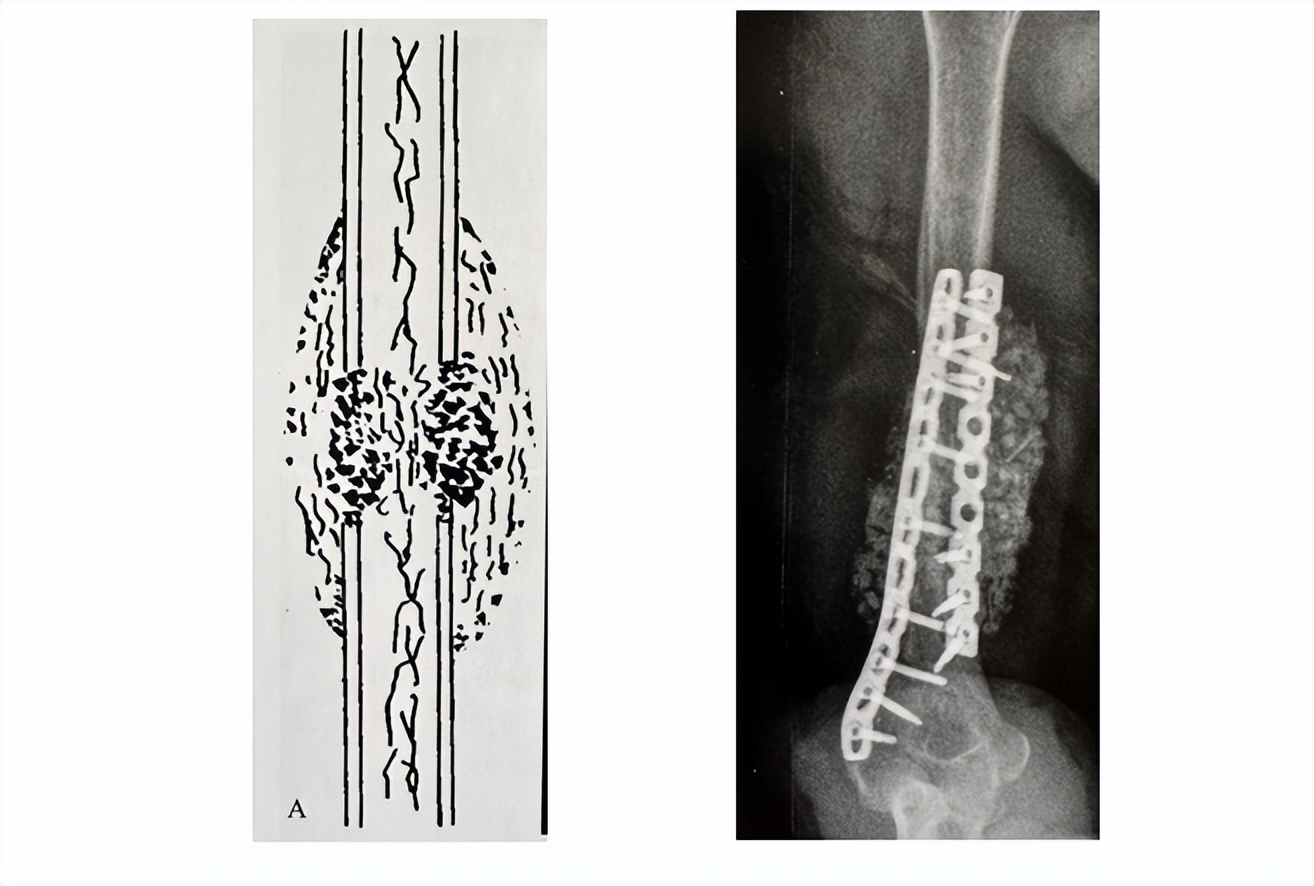

(骨不连模型)

目前传统的治疗方法就是清理骨折端,取病人自己的骨头,植入骨不连区域,这个方法疗效值得肯定,但是最大的问题是会给病人增加额外的创伤,病人的经济花费也比较高。

(传统治疗方法:大范围清理骨折端)

(取自体髂骨)

(360度环抱植骨,更换原有内固定)